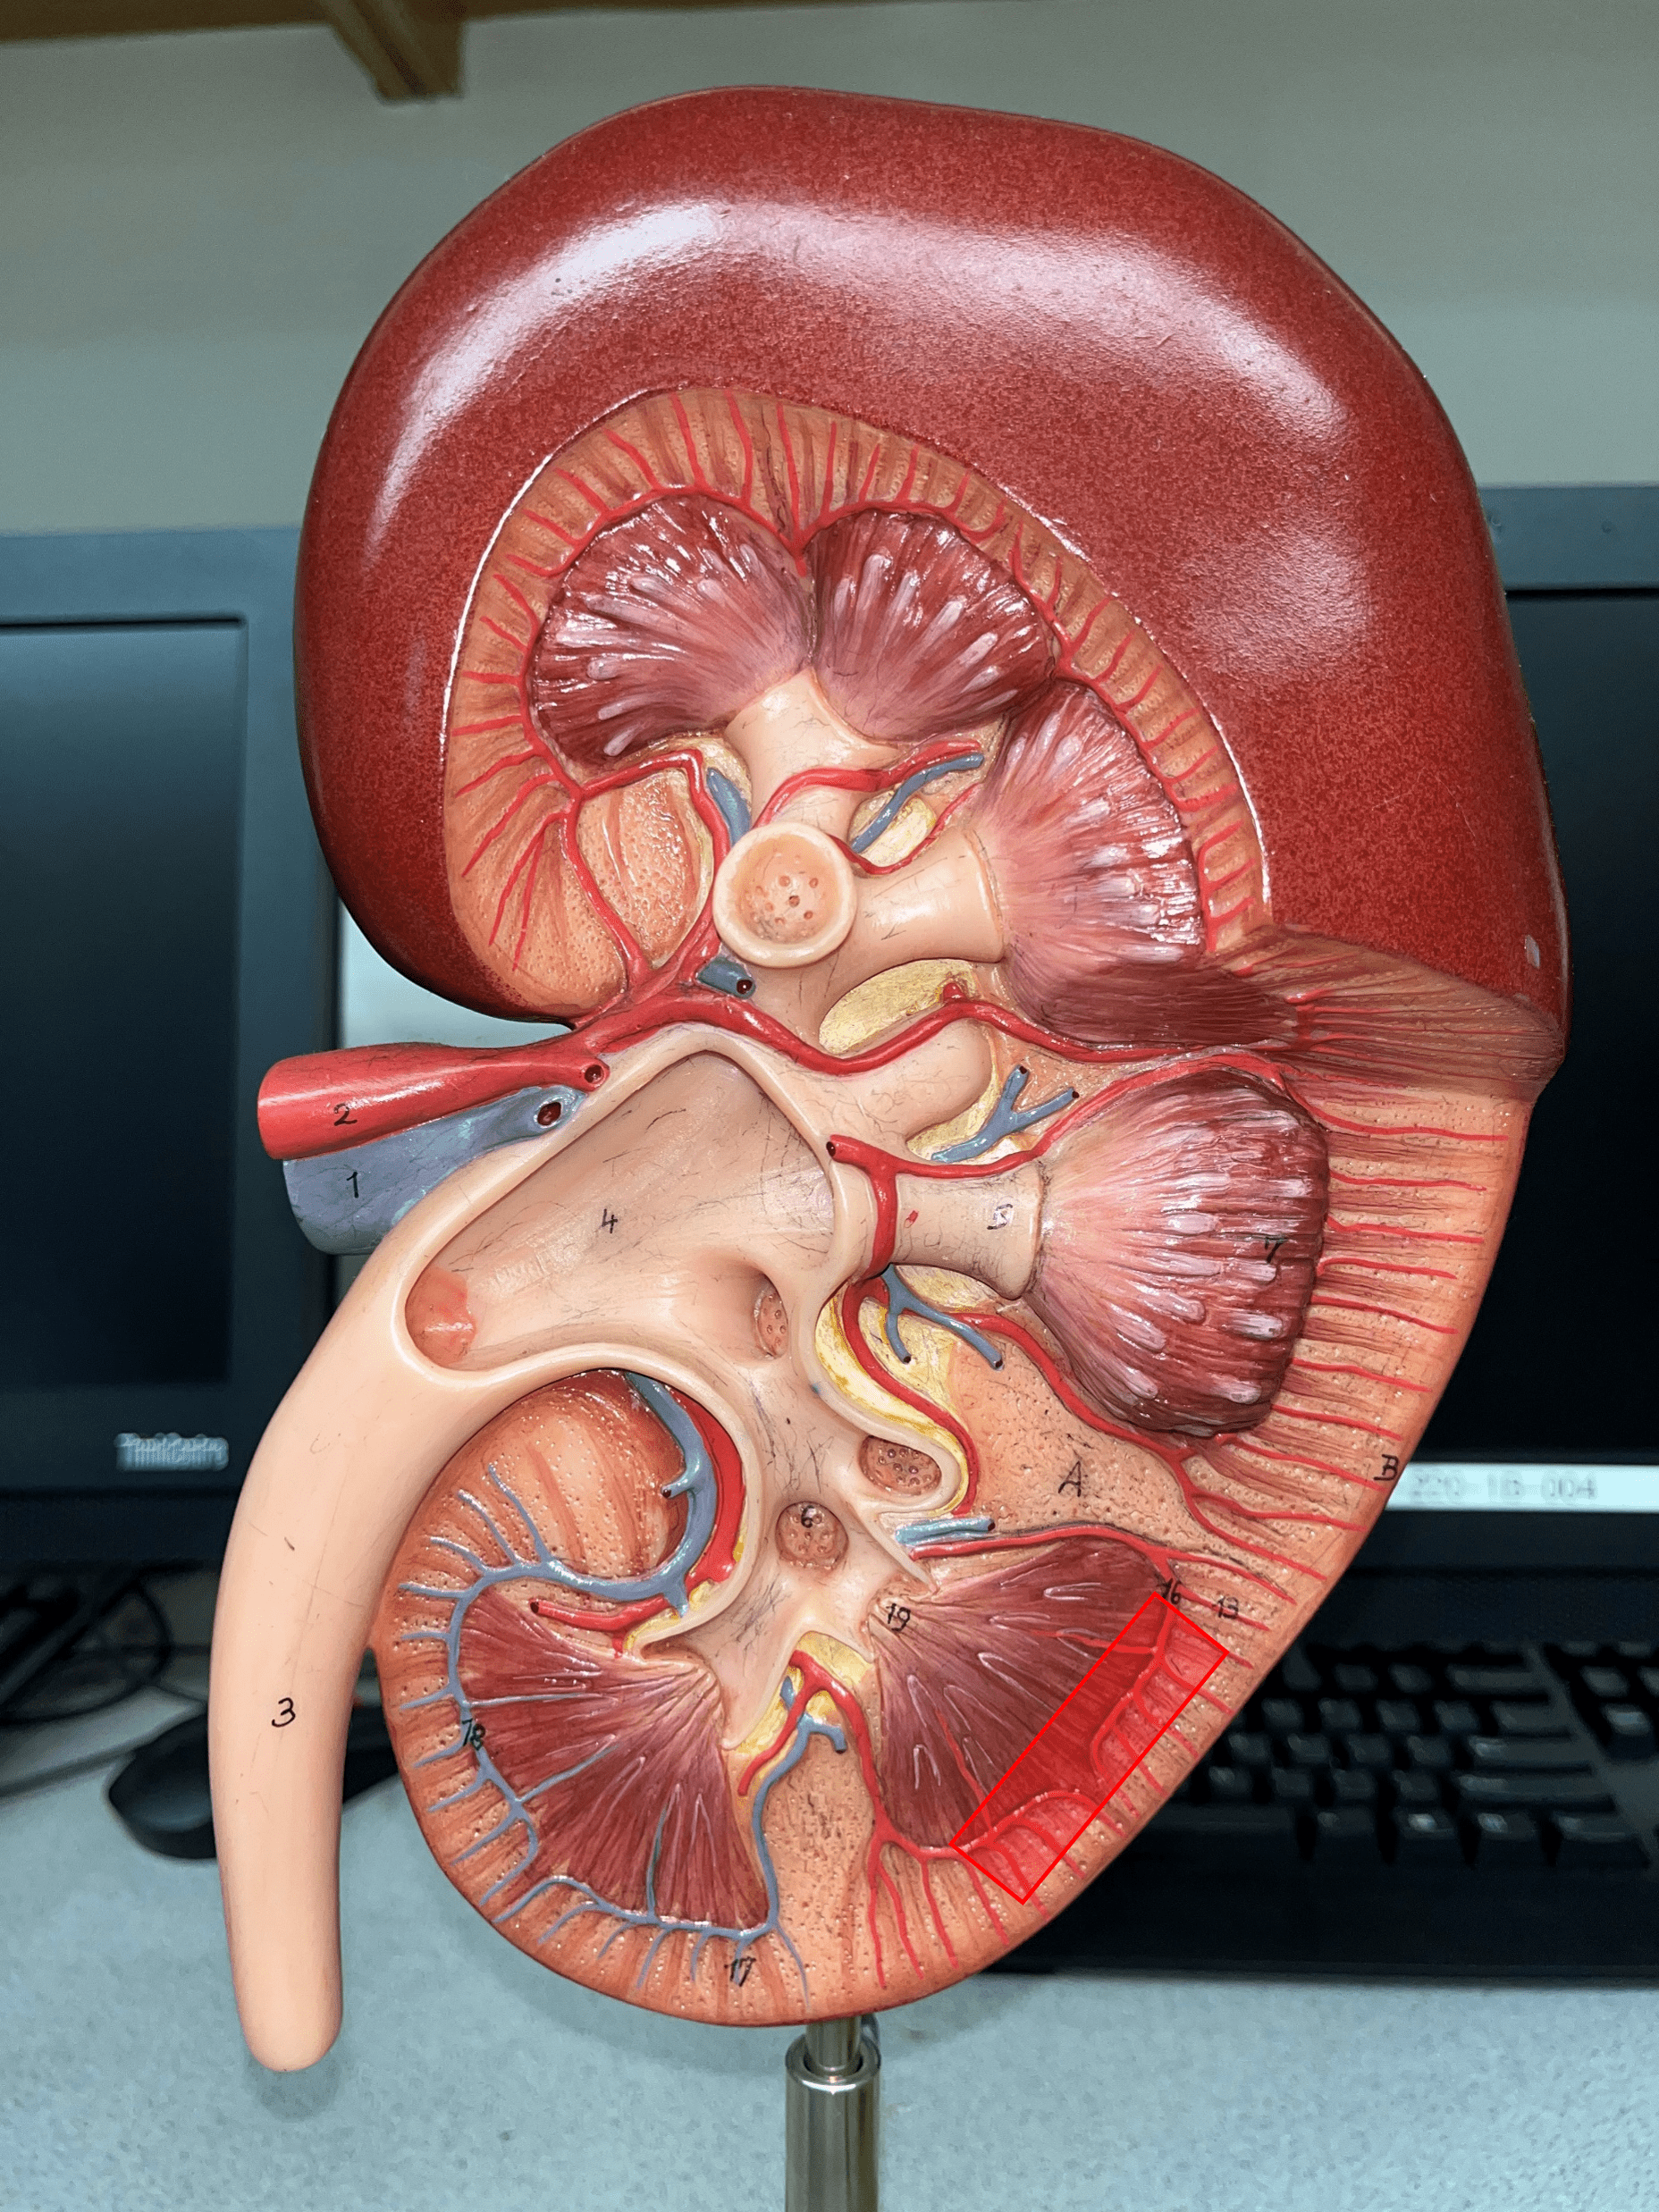

interlobular vein

• Extends through the renal cortex.

• Converges into an arcuate v.

• Converges into an arcuate v.

arcuate vein

• Extends along the base of the renal pyramids.

• The convergence of interlobular vv.

• Converges into an interlobar v.

• The convergence of interlobular vv.

• Converges into an interlobar v.